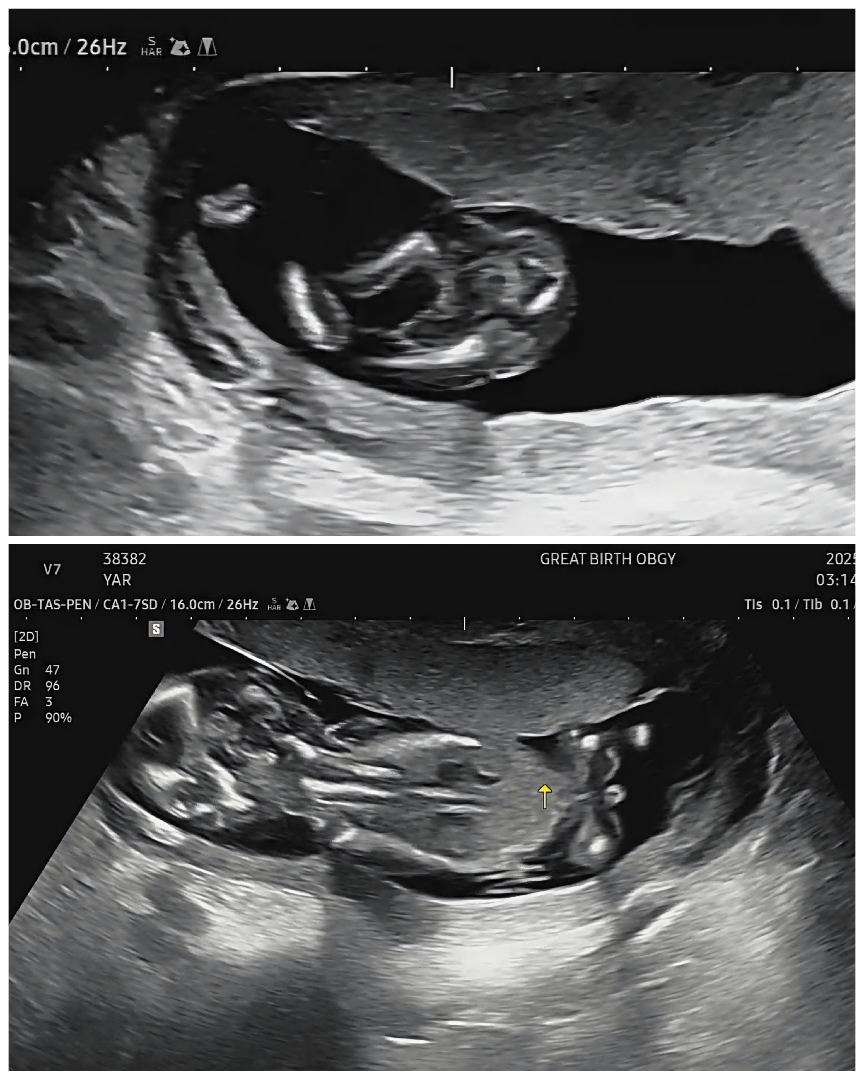

14주차 초음파 성별 봐주세요 🩷🩵

애기가 데굴데굴 굴러서 옆모습은 못봤는데, 의사선생님께서는 다리사이를 보시고 깨끗하다며 공주 같다고 말씀해주셨어요! 근데 아기가 뒤 돌아있는 모습에서 엉덩이 가운데에 볼록한 형태가 보이는데, 이거는 생식기가 아닌가요? 혹시 반전이 있을 수 있는 확률이 있을까요?